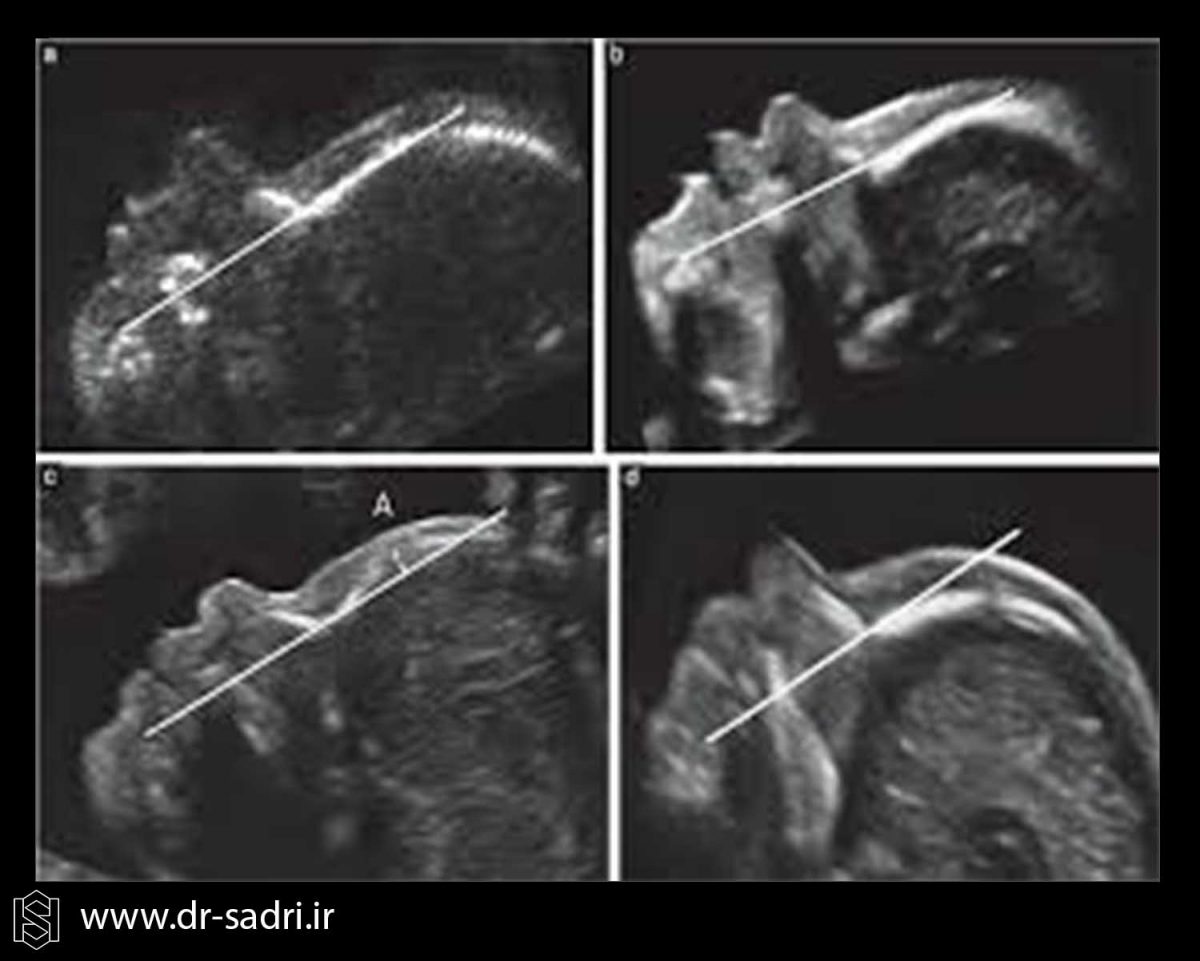

سونوگرافی ان تی

یکی از اولین روش ها که در سه ماه اول بارداری برای تشخیص نشانگان داون استفاده می شود، سونوگرافی ان تی است . از آن جایی که با افزایش سن مادر، خطر ابتلای جنین به این بیماری بیشتر می شود سونوگرافی ان تی برای همه ی زنان حامله توصیه می شود. سونوگرافی ان تی را می توان در جنین بین ۴۵ تا ۸۴ میلی متر که حدودا با سن ۱۱ تا ۱۴ بارداری تطابق دارد انجام داد ولی بهترین زمان انجام سونوگرافی ان تی هفته ۱۲ تا ۱۳ بارداری می باشد. هرآنچه در مورد سونوگرافی ان تی باید بدانید

عکس جنین مبتلا به سندروم داون

[…] NT پیشنهاد می دهد. این سونوگرافی برای غربالگری سندرم داون انجام میشود و دانستن اینکه چقدر از بارداریتان می گذرد […]

[…] سندرم داون را می توان در سونوگرافی هفته ۱۲ ام به طور دقیق شناسایی […]